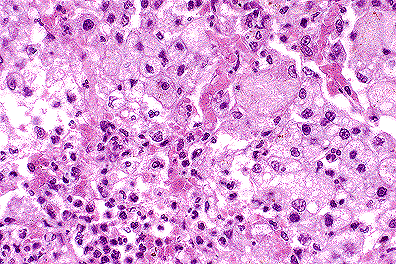

Numerous intracytoplasmic morbilliviral inclusions in the renal pelvic epithelium of a mink. (40X, HE, 64K)

Contributor's Diagnoses and Comments: Renal tubular medullary mineralization, moderate and diffuse. Renal pelvic epithelial apoptosis with intracytoplasmic inclusions. Etiology: canine distemper virus.

Renal tubular mineralization in the medulla is often seen in anorexic mink, probably due to dehydration. Cytoplasmic inclusions were also present in bronchiolar epithelium and in the urinary bladder mucosa. Severe bronchopneumonia was also present. The host range of canine distemper virus includes the dog, coyote, fox, wolf, dingo, jackal, raccoon, panda, weasel, mink, ferret, badger, skunk and otter. It was felt that raccoons may have transmitted the infection to mink in this case. A similar, if not identical virus, has been reported to cause distemper-like illness in captive and wild leopards, tigers, lions, jaguars and civets. Similar viruses infect harbor seals, porpoises and javelinas.

1. Kidney, tubular epithelium and pelvic urothelium: Eosinophilic intracytoplasmic inclusion bodies, with occasional syntical cells, Mustela vison, mustelid, etiology consistent with canine distemper virus.

2. Kidney, corticomedullary junction: Mineralization, tubular epithelium, multifocal, moderate.

3. Kidney, tubular epithelium: Fatty change, diffuse, moderate.

Conference Note: Canine distemper virus (CDV) is a morbillivirus in the Paramyxoviridae family. Infection with CDV occurs by inhalation with the virus localizing in tonsils and bronchial lymph nodes. After 2-5 days there is a cell associated viremia, with the virus infecting lymph nodes, spleen, thymus, bone marrow, and macrophages in the lamina propria of the stomach and intestine. At this stage of infection, severe depletion of lymphocytes may develop with concomitant immunosuppression. At 8-10 days post-infection, the virus again disseminates, with continued infection of mononuclear cells and epithelial cells, causing hyperkeratotic dermatitis, diarrhea, pneumonia, and keratitis. The brain is sometimes affected, usually after the visceral infection has ended. The virus first infects macrophages in the meninges and later spreads to ependymal cells, glial cells, and neurons. Neuronal involvement leads to behavioral changes and varying degrees of muscular spasm or paresis. Forty to sixty days after apparent recovery, some dogs develop demyelinating lesions within the brain. This complication of CDV infection is usually fatal.

Morbilliviruses possess two proteins which facilitate binding to host membranes, hemagglutinin and F protein. The F factor mediates fusion of the viral envelope with the cellular membrane and assists in viral attachment. It also causes host cell fusion and is responsible for the formation of syncytial cells. The ability to fuse host cells allows the virus to spread without being exposed to antibody. To be biologically active the F protein must be cleaved by a host protease into two disulfide-linked polypeptides, F1 and F2. If a host cell lacks the necessary proteases, the virus formed is not infectious, since the F factor is required for viral attachment.

Conference participants also noted numerous lipid vacuoles within the renal tubular epithelium. This is a common finding in anorectic or fasted mustelids and is related to the high metabolic rate of these animals and their ability to rapidly mobilize fat stores.